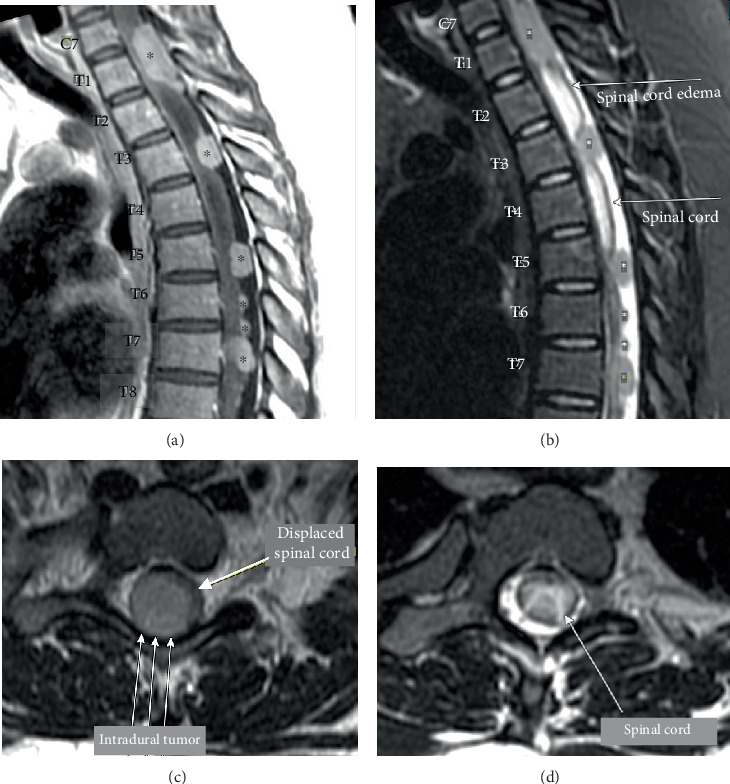

髓母细胞瘤是后颅窝的肿瘤,有沿脊髓发展为轻脑膜转移的倾向,通常称为“滴状转移”。髓母细胞瘤约占所有成人脑肿瘤的1%-2%,原发性脑脊膜髓母细胞瘤的报道非常有限。在此,我们提出一个罕见的病例,34岁的女性诊断为多灶性原发性脊髓轻脑膜髓母细胞瘤,没有颅脑受累。

Medulloblastomas are tumors of the posterior fossa that have a propensity to develop leptomeningeal metastases along the spinal cord, commonly known as "drop metastases." Medulloblastoma accounts for approximately 1%-2% of all adult brain tumors, and reports of primary leptomeningeal medulloblastoma are extremely limited. Herein, we present a rare case of a 34-year-old woman diagnosed with multifocal primary spinal leptomeningeal medulloblastoma without cranial involvement.